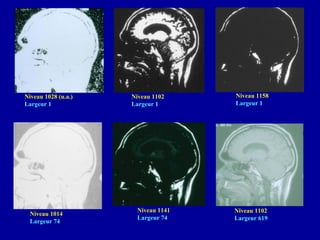

Niveau 1028 (u.a.)

Largeur 1

Niveau 1102

Niveau 1158

Niveau 1014

Largeur 74

Niveau 1141

Largeur 619